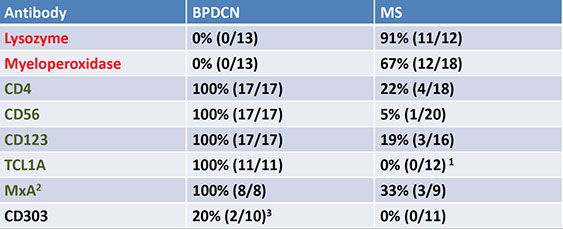

Blastic plasmacytoid dendritic cell neoplasm